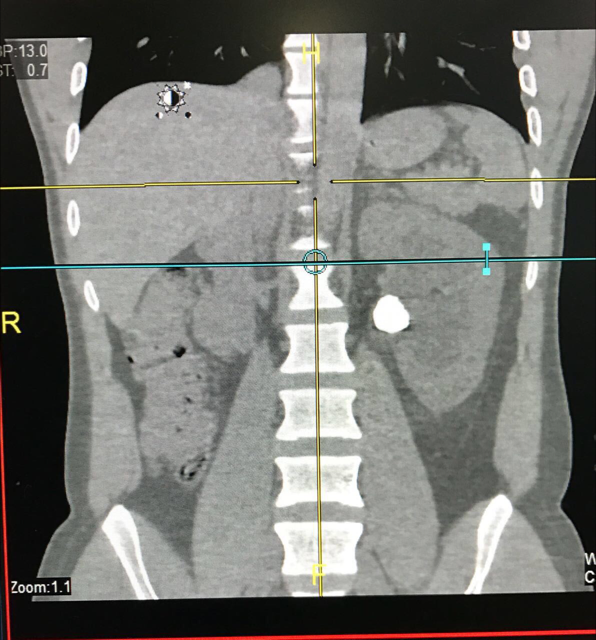

نجح فريق طبي بمجمع الملك فيصل الطبي في إجراء أول منظار لاستخراج حصوات الكلية عن طريق فتحة صغيرة لا تتعدى السنتيمتر الواحد في جسم المريض، وتعد هذه الخدمة الطبية حديثة بعد أن كان يتم تحويل المرضى لمكة وجدة.

وكان المريض يعاني من طول المواعيد وتحمل مشاق السفر، حيث نجح الفريق المعالج بقسم المسالك البولية بالمجمع برئاسة الدكتور أشرف أسعد سليمان استشاري المسالك البولية ومساعداه الدكتور محمد شريف استشاري المسالك والدكتور أحمد حسني وأخصائي التخدير الدكتور وفيق، في إجراء عملية منظار دقيقة وتكسير الحصوة واستخراجها بالكامل لمريض عشريني بعد أن تعرض للمعانه طويلاً من عدم القدرة على العمل وقد نجح الفريق في إنهاء معاناة المريض الذي يتمتع الآن بصحة جيدة .

الجدير ذكره أن عمليات إزالة الحصوة بالمنظار من الخدمات الجديدة التي حرصت إدارة المجمع على دعمها وتوفير الأجهزة اللازمة لإجرائها لتوفير الوقت والجهد على المريض.